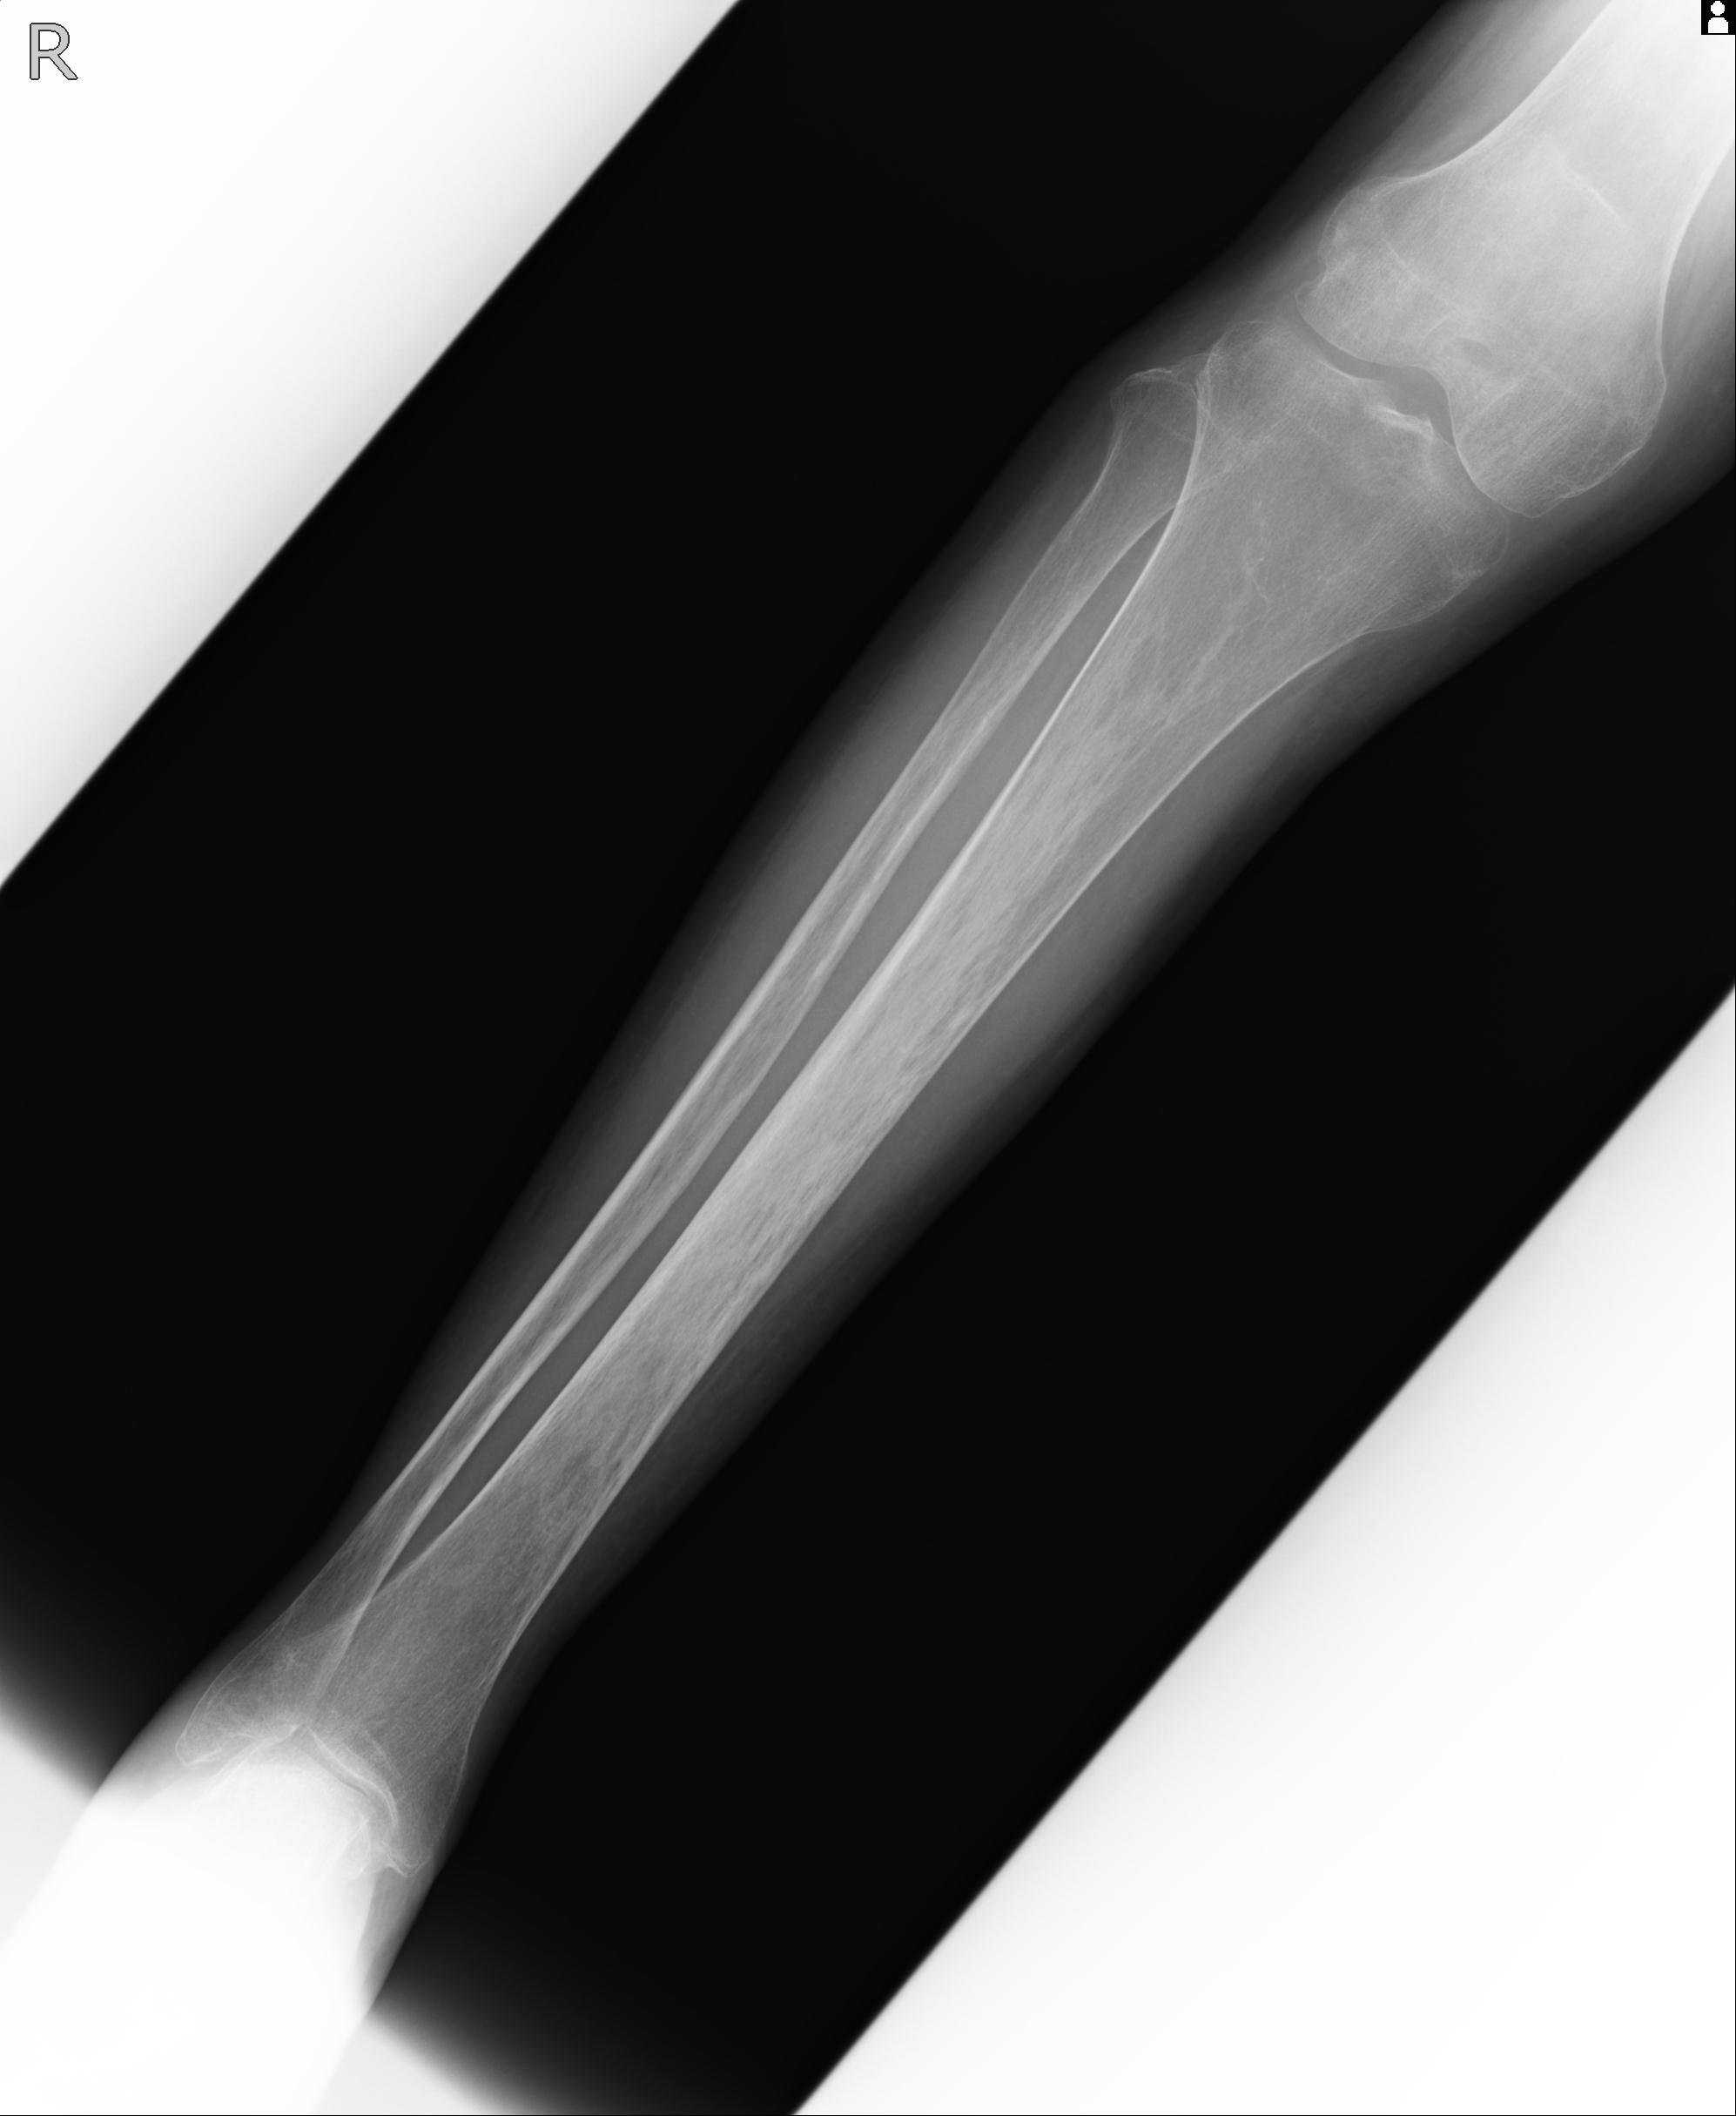

110211 1/6 1/8 左前腕 4R 15歳男性 橈骨骨幹部骨折